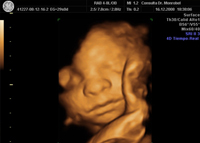

Ecografias 3D-4D

La ecografía tridimensional (3D) es una nueva técnica que mejora la potencialidad diagnóstica de los ultrasonidos en diferentes campos de la medicina. Desde que en 1989 fue introducida en el terreno de la Ginecología, se ha desarrollado de tal manera que resulta asombroso el realismo con el que se consiguen imágenes de la cara y del cuerpo fetales; el gran avance tecnológico que se produce día a día en esta parcela nos hace suponer un futuro prometedor.

La ecografía 3D está basada en la obtención del volumen fetal (modo V), lo cual supone disponer de una mayor información con respecto a la ecografía tradicional (2D) que reporta imágenes en dos planos.

Con la ecografía 3D se dispone de ventanas gráficas, con mayor capacidad discriminatoria; se obtiene una imagen multiplanar que permite evaluar el punto de conjunción resultante de los tres planos ortogonales: x, y, z.

La ecografía 3D en tiempo real (4D), visualiza actividad motora: los movimientos corporales y expresiones faciales de feto.